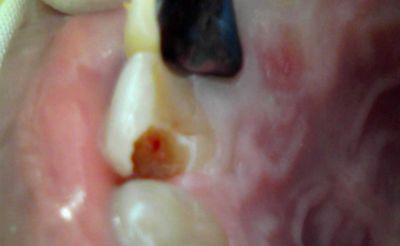

■女性:左上の銀歯が欠けて痛い

左上6番、インレーの辺縁が大きく欠けている。冷水痛(+)、咬合痛(+)

インレーを除去したが、齲蝕は深そうだ。

案の定深い。

このケースに関しては直覆はあきらめて断髄に移行した。

CR充填して終わり。

1週間後、冷水痛・咬合痛は消失していたが、経過観察が必要だろう。